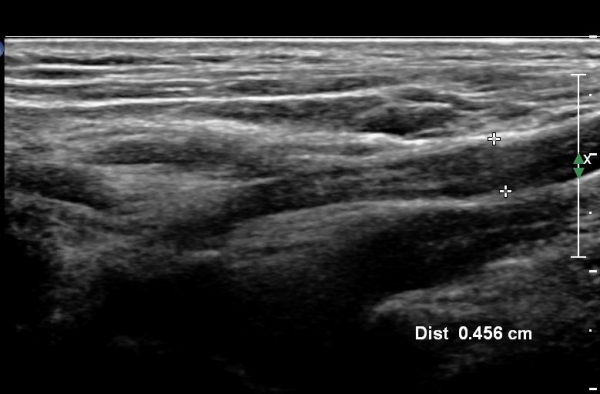

¸ñ ¾Õ ¿ÜÃø¿¡¼­ Á¦5, 6 ½Å°æ±Ù Á¾´Ü¸é°Ë»ç¿¡¼­ Á¦5, 6 ½Å°æ±ÙÀÇ Àú¿¡ÄÚ ºÎÁ¾(4,5mm, 6.5 mm)ÀÌ

°üÂûµÇ°í »çÁø 4,5 ) °ÇÃø(»çÁø 6, 7)(2.4mm, 3.1mm)°ú ºñ±³ÇÏ¸é ¾à 2¹èÀÌ»ó ºÎÁ¾ÀÌ ¶Ñ·ÇÇÔ.